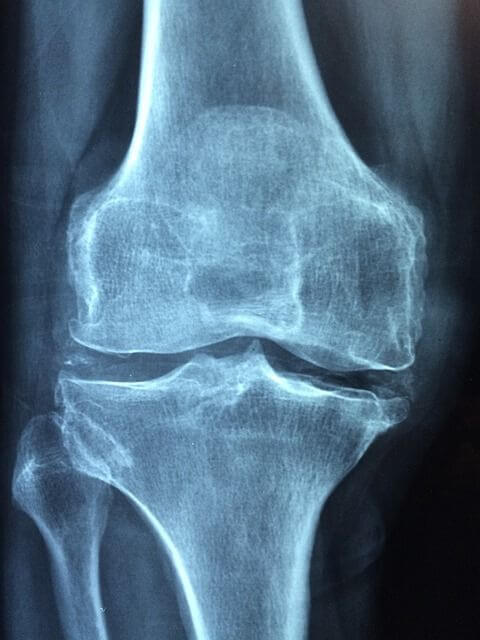

베이커 낭종을 확인하기 위해선 임상적인 평가가 주로 사용됩니다. 대부분의 낭종은 반막양근과 종아리근육의 안쪽 머리 사이에 위치해 있으며, 낭종이 커진 경우에는 육안으로 보거나 만질 수 있습니다, 대부분의 경우 X선(XR)은 정상으로 나타납니다. MRI는 특별히 필요하지 않으며,